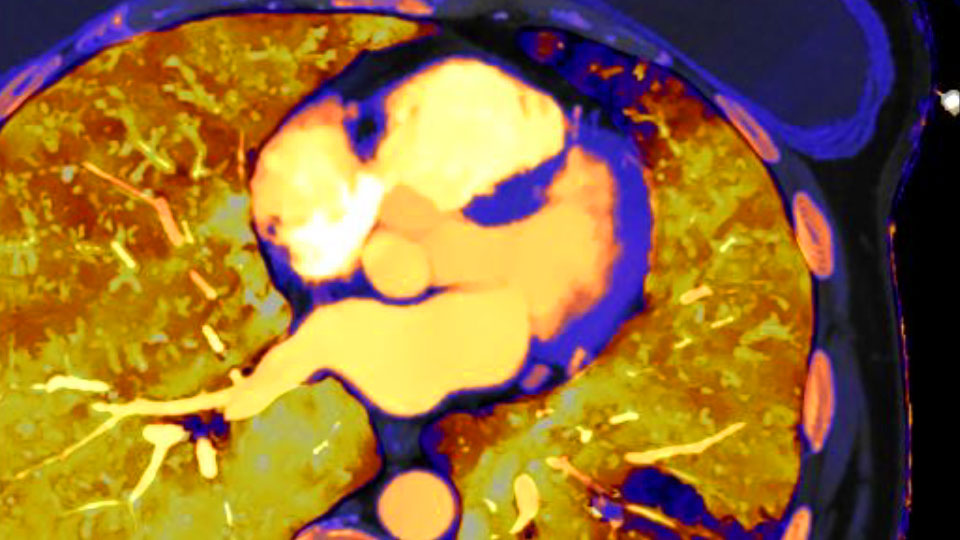

Amplíe y mejore sus capacidades cardiacas con la adquisición de imágenes cardiacas espectrales de campo de visión completo. Reduzca el artefacto de borrosidad producido por el calcio en las arterias coronarias.

Ahora puede saber fácilmente tanto el "dónde están las cosas" del CT convencional como el "lo que son las cosas" revelado por los datos del detector espectral. Las capas de datos espectrales enriquecidos mejoran la caracterización y la visualización del tejido, y reducen la necesidad de realizar exploraciones de seguimiento en exámenes subóptimos y hallazgos accidentales.

Imagen de CT convencional (izquierda) Imagen de CT con detector espectral (derecha)